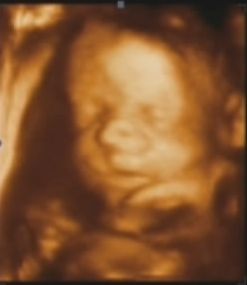

Csak gyors bekukk... Ma voltunk Uh-n, íme az eredmény:

Kép

Elég egyértelműen látszott, hogy kisfiú, minden alkatrésze rendben van, teljesen a korának megfelelően fejlődik.

Gyorsan követni tessék mindenkinek :wink: :lol: :!: :!: :!:

Panda, nagyon édes! :) És esküszöm, látszik a pofiján, hogy fiú.... Durva...

Gratulálok a kis kukishoz! :lol: :lol:Annyira látszik, hogy pasis arca van. :lol:

Panda,hihetetlen ez a kép,még ki sem bújt és már lehet látni a kis pofiját,biztos nagyon jó érzés látni őt az ultrahangon.Ilyenkor,amikor látod,nincs olyan érzésed,hogy milyen jó lenne már a kezedbe venni és megszeretgetni?(Tényleg fiús vonásai vannak!)